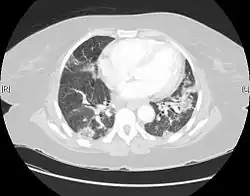

| CT scan of a patient with UIP. There is interstitial thickening, architectural distortion, honeycombing and bronchiectasis. | |

Usual interstitial pneumonia (UIP) is a form of lung disease characterized by progressive scarring of both lungs.[1] The scarring (pulmonary fibrosis) involves the pulmonary interstitium (the supporting framework of the lung). UIP is thus classified as a form of interstitial lung disease.

UIP may be diagnosed by a radiologist using computed tomography (CT) scan of the chest, or by a pathologist using tissue obtained by a lung biopsy.

Radiology

Radiologically, the main feature required for a confident diagnosis of UIP is honeycomb change in the periphery and the lower portions (bases) of the lungs.[3]